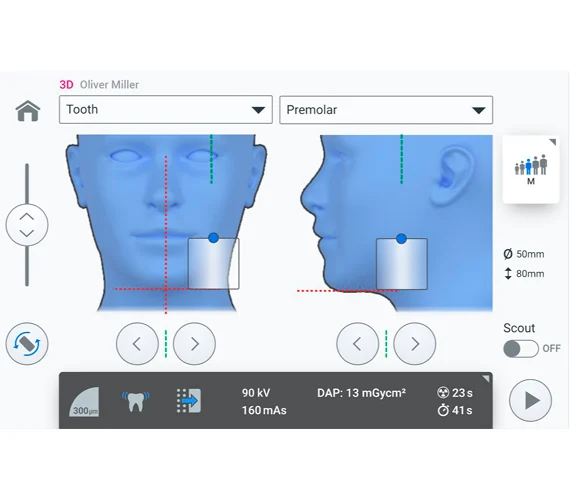

Pozycjonowanie nigdy nie było prostsze

Planmeca Viso G1 jest wyposażony w uproszczony system laserowy umożliwiający łatwe pozycjonowanie pacjenta bez żadnego wysiłku. Pole widzenia jest wybierane bezpośrednio z poziomu wirtualnego pacjenta na panelu sterowania i można je dowolnie dostosowywać po wykonaniu obrazowania próbnego. Dzięki otwartej architekturze pacjent ma dużo miejsca i zawsze jest zwrócony twarzą do użytkownika.